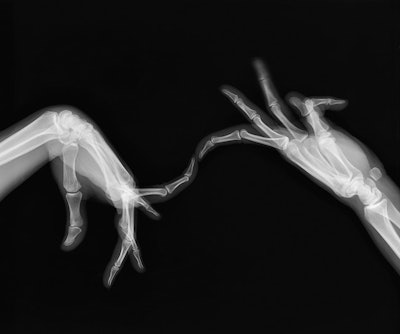

Such flexibility is on display in the "hand dancing" series, which shows hands in seemingly unattainable positions, reflecting the movement of a puppeteer warming up, for example, or of different types of dance.

"X-ray imaging crushes any kind of space and expression," he told AuntMinnieEurope.com. "I had to find people with special abilities, such as specific morphologies or a certain flexibility in their hands."